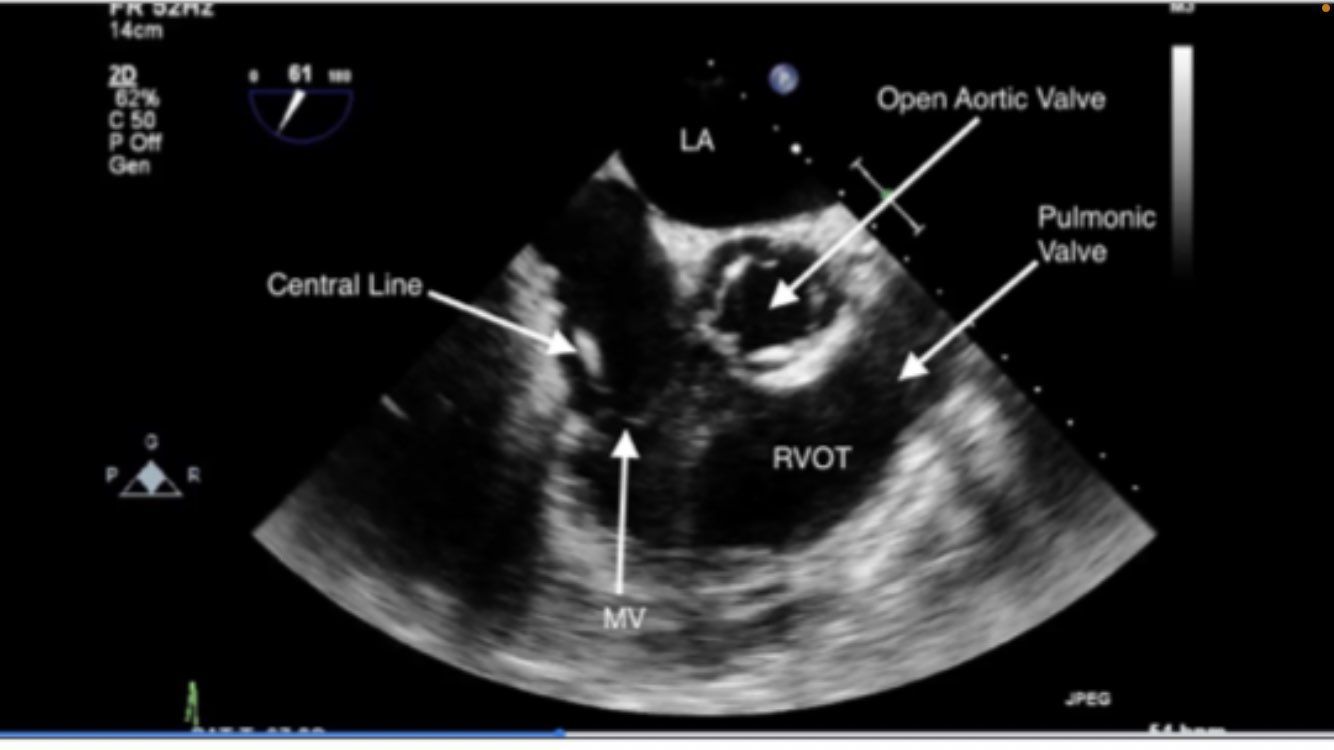

Mid esophageal RV inflow and outflow

TRICUSPID NOT MITRAL VALVE